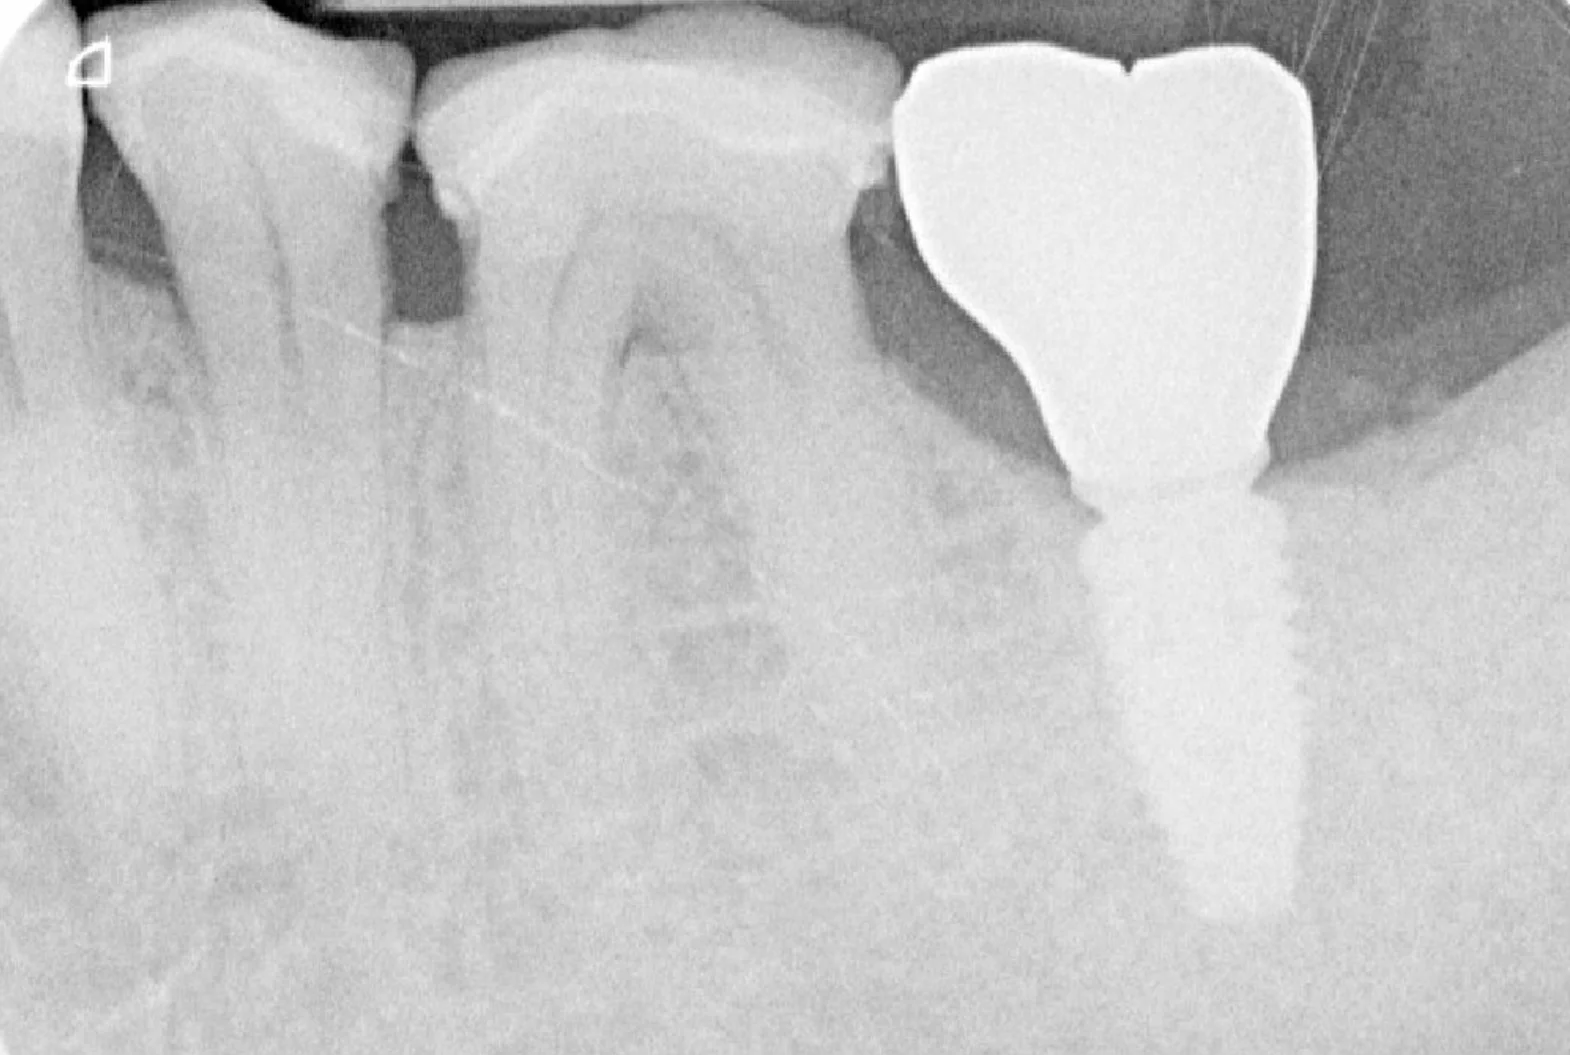

Un Cone Beam 3D est systématiquement réalisé pour analyser avec précision la quantité et la qualité osseuse disponible au site implantaire, ainsi que pour repérer les structures anatomiques à respecter (nerf alvéolaire inférieur, sinus maxillaire, etc.).

À partir des données recueillies lors de la première consultation ( Cone Beam 3D, empreinte optique, examen clinique et anamnèse médicale ) une planification implantaire tridimensionnelle est réalisée à l’aide de logiciels spécialisés.

- Positionner virtuellement l’implant de manière idéale, en respectant à la fois les contraintes anatomiques (canal mandibulaire, sinus, racines adjacentes, structures nerveuses) et les contraintes prothétiques (axe d’émergence, espace disponible, équilibre occlusal, esthétique) ;

Ce dispositif permet de localiser avec précision non seulement l’os disponible, mais aussi les structures critiques telles que le nerf alvéolaire inférieur, le sinus maxillaire ou les racines des dents voisines, assurant une pose plus sûre, plus précise et conforme au projet prothétique.

Un suivi clinique est ensuite assuré 4 mois après la pose de l’implant pour évaluer l’évolution, valider l’ostéointégration et planifier la suite du traitement prothétique.